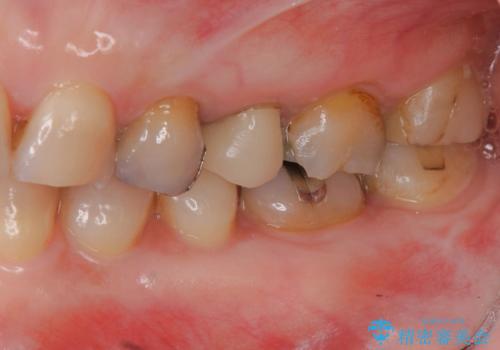

- 虫歯治療を中断し放置、痛みが出てきたため当院を初診来院されました。

虫歯の深化により根管治療、歯周外科手術を行い歯肉の状態を改善し精密なセラミッククラウンを製作する治療を計画します。